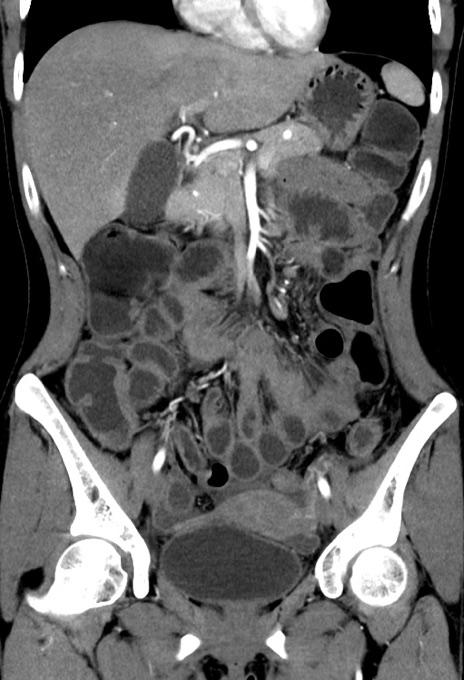

症例17(冠状断像)

【症例】20歳代女性

【主訴】嘔吐、下腹部痛

【現病歴】昨日夕食後に嘔吐し下腹部痛が出現。本日になっても嘔吐持続し改善しないため来院。

【身体所見】意識清明、BT 37.2℃、BP 108/67mmHg、腹部:平坦、やや硬、下腹部正中から右にかけて圧痛あり、反跳痛軽度あり、tapping pain(+)。

【データ】WBC 13600、CRP 14.94